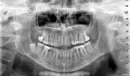

Зуба мудрости во рту нет, десна бледно розовая, во рту проблем нет. Но появились боли, уже месяц в области 6 и 7 зуба внизу справа, то верхние зубы справа (проверила, они здоровы). Также боли у уха, под глазом, щека, в шее от мочки и вниз. Обошла всех врачей, никто не знает отчего. Думала на зуб мудрости, но говорят, что с ним можно жить всю жизнь т.к. он ретинированный и ничем не грозит. Уезжаю на море, на все лето, боюсь, чтобы не заболели зубы от жары. Направила Вам снимки: первый снимок годовалой давности, далее КТ и ортопант - они сделаны только сейчас.

Есть ли какие то изменения на снимках? Есть ли какие то изменения с зубом мудрости? Можно ли данный зуб мудрости не удалять?

Рекомендуем вам обратиться на прием к стоматологу-хирургу. Восьмой зуб расположен таким образом, что никогда полноценно в зубной ряд не прорежется. Но так как он сохраняет тенденцию к прорезыванию, то будет вызывать боль, сдавливая окружающие ткани, а так же гипертонус мышц. Как правило, такие зубы рекомендуется удалить.